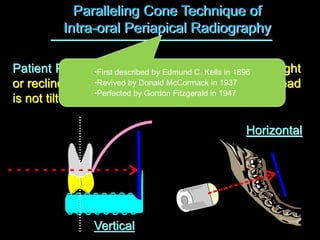

1. The document discusses various intra-oral radiographic techniques including the paralleling cone technique and bisecting angle technique.

2. The paralleling cone technique provides accurate images with little magnification and no superimposition but is more difficult for patients. The bisecting angle technique is easier for patients but results in more image distortion.